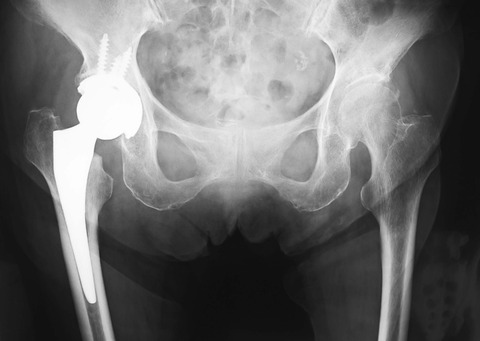

上記は、臥位での単純X線像正面像です。カップの前方開角が小さく、0~5度ぐらいです。一方、この患者さんの立位での単純X線像正面像は下記です。